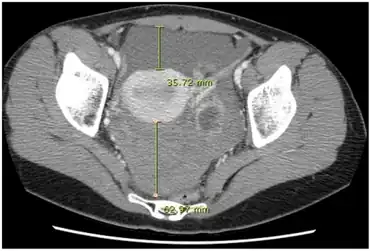

| CT quantification of hemoperitoneum. | |

- Computed tomography

With modern diagnostic aids such as computed tomography (CT) scans, certain injuries such as low-grade lacerations of the spleen may be diagnosed early and observed, with surgical options deferred unless clinical deterioration obligates them. In rare occasions, rupture of an Abdominal Aortic Aneurysm may be repaired via an endovascular technique, though this is generally not performed in the setting of acute rupture.